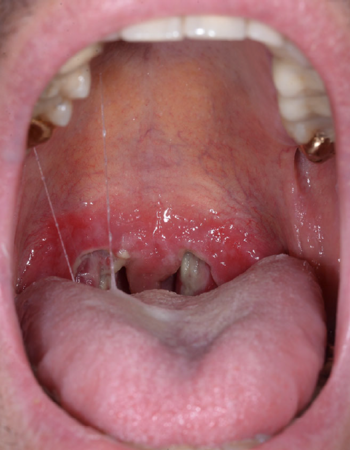

Eine 22-jährige Patientin stellte sich mit bläulichen, erbsengroßen Tumoren an der rechten Schulter, der rechten Flanke, am linken Unterbauch sowie am rechten mediodistalen Oberschenkel vor, die seit früher Kindheit bestanden. Die beschriebenen Tumoren waren seit etwa einem Jahr zunehmend druckschmerzhaft mit einer Schmerzintensität von 8/10 auf der numerischen Ratingskala (NRS).